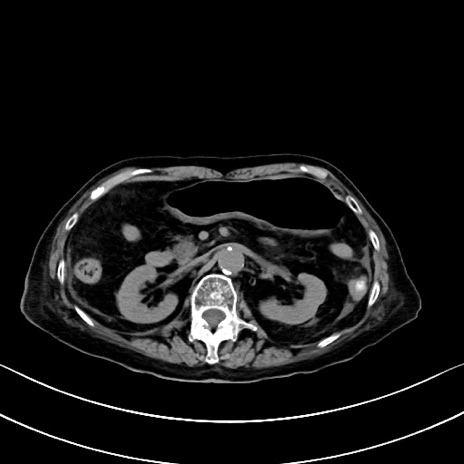

症例40(横断像)他院1日前

横断像

他院CT